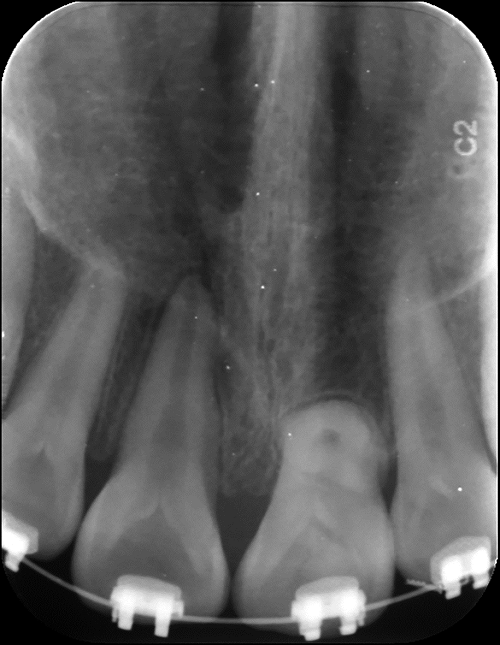

图 2

上颌恒中切牙在根尖片中的21牙“牛眼”征象"